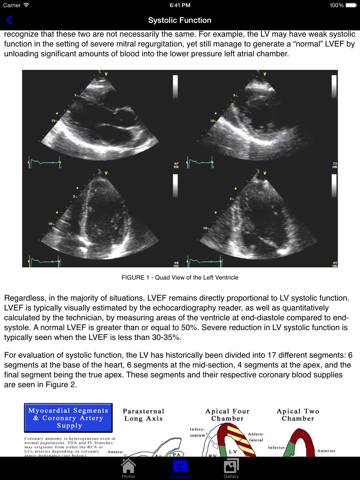

EchoSource (from the creators of ECGsource and CathSource) is a medical reference devoted exclusively to echocardiography. Developed by practicing cardiologists for both specialists and trainees in the field of cardiovascular disease, EchoSource offers the following content: * Searchable index of specialized topics including: History of Echocardiography Transthoracic Echo – Learning the Procedure Transesophageal Echo – Learning the Procedure Standard Transthoracic Echocardiography Views Standard Transesophageal Echocardiography Views Hemodynamics: Doppler Overview Hemodynamics: Color Flow Imaging Hemodynamics: Transvalvular Gradients Hemodynamics: Intracardiac Pressures Hemodynamics: Cardiac Flow & the Continuity Equation Hemodynamics: Proximal Isovelocity Surface Area (PISA) Left Ventricle: Systolic Function Left Ventricle: Diastolic Function Valvular: Aortic Stenosis Valvular: Aortic Regurgitation Valvular: Mitral Stenosis Valvular: Mitral Regurgitation Valvular: Pulmonic Stenosis Valvular: Pulmonic Regurgitation Valvular: Tricuspid Stenosis Valvular: Tricuspid Regurgitation Valvular: Prosthetic Valves Clinical Disorder: Aortic Dissection Clinical Disorder: Atrial Septal Defect Clinical Disorder: Constrictive Pericarditis vs. Restrictive Cardiomyopathy Clinical Disorder: Hypertrophic Cardiomyopathy Clinical Disorder: Intracardiac Masses - Endocarditis & Vegetations Clinical Disorder: Intracardiac Masses - Thrombus Clinical Disorder: Intracardiac Masses - Tumors Clinical Disorder: Pericardial Effusion Clinical Disorder: Pseudoaneurysm Clinical Disorder: Pulmonary Artery Hypertension Clinical Disorder: Subaortic Membrane Clinical Disorder: Ventricular Septal Defect * Searchable database consisting of more than 90 figures, images, and echocardiography videos of both common and rare findings in the field of echocardiography EchoSource provides a detailed overview of clinical disorders and their evaluation using echocardiography, incorporating educational figures and videos as well as reviews of pertinent medical literature. Whether you are a beginner just learning standard echocardiography imaging views, or a practicing clinician needing a quick reference to guideline-based echocardiographic criteria for diagnosing the severity of valvular heart disease, EchoSource is the ideal application to assist you.

As a physician, I am always looking for practical and informative apps to make my practice of medicine easier. This app fits the bill. It is extremely comprehensive, and the images are awesome. A must for all docs and healthcare professionals.

Clinical disorder videos freeze-frame to point out the echo findings. Figures are detailed. Best pocket reference that I have found regarding echo criteria for severity of valvular heart disease and diastolic function parameters. Other reviewer commented on PSAX base view being mislabeled, but it is labeled correctly. Have not come across any inaccurate info. Strongly recommend.